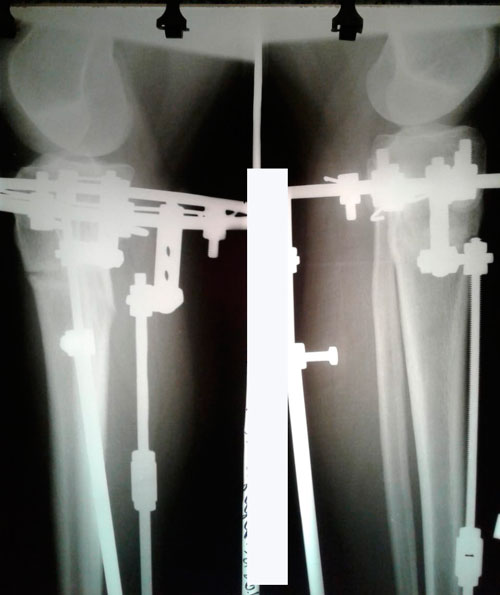

Исходник 33 года.

Дата операции 26.04.2018г.

Перед крутками